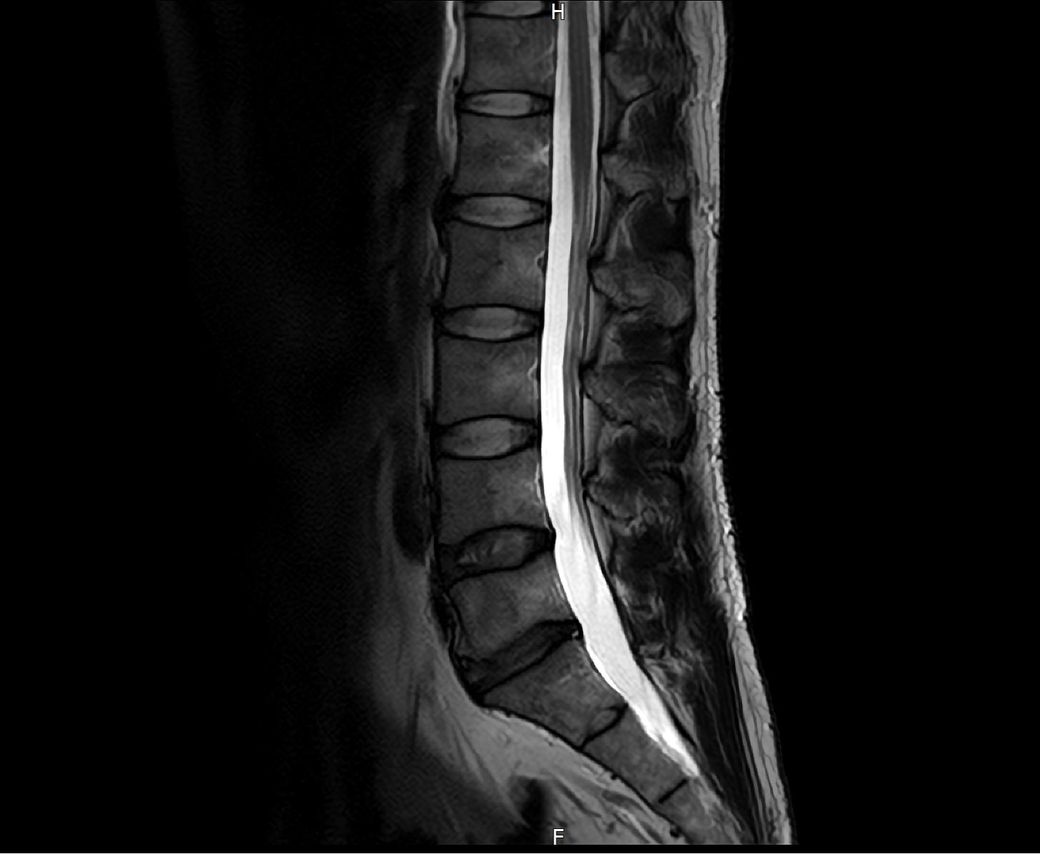

요추MRI에선 저렇게 보이는 상태이고 근전도에서 요추5번에서 문제가 있다고 나오긴 했습니다만 그게 이런 증상까지 불러오나요?

요추MRI상은 크게 문제 없었으나 최근 5월12일에 근전도검사를 했을 때 요추5번에 문제가 있다고 나오긴 한 상태입니다...